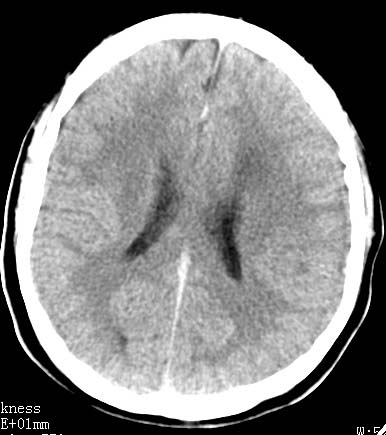

以下是引用clj20在2007-8-29 9:47:00的发言:[br]蛛网膜下腔出血,左侧额叶不均匀密度影,占位效应明显,界限不清。支持:占位性病变,建议增强!

以下是引用xulianj在2007-8-29 20:15:00的发言:[br]蛛网膜下腔出血,左侧额叶不均匀密度影,占位效应明显,界限不清。支持:占位性病变,建议增强!

以下是引用jiangjing在2007-8-29 14:33:00的发言:[br]左侧额叶不均匀密度影[低密度为主,边缘见等密度环环绕]占位效应明显,界限不清。支持:占位性病变,建议增强! [br][br]